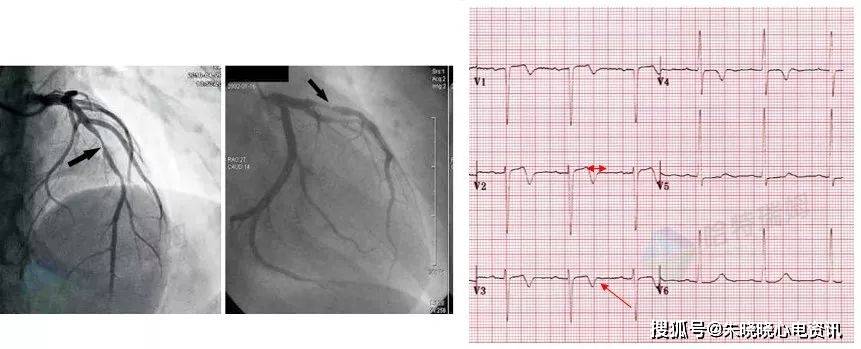

心肌梗死定位:是传说中的正后壁吗?